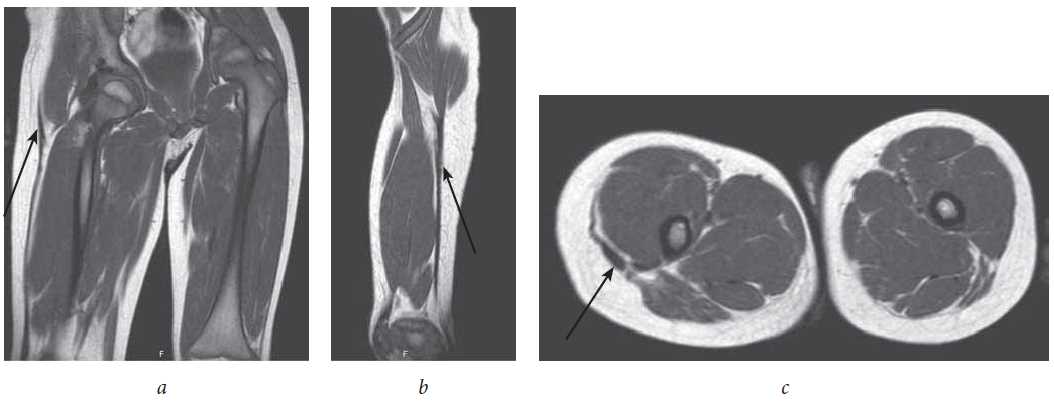

Magnetic resonance imaging (MRI) data were obtained using an MR tomograph Philips Panorama with a magnetic field induction of 1.0 T. Visualization of the fibrous cord in the soft tissues of the right thigh was most clearly determined using T1 weighted images (T1WI) in the coronary, sagittal, and axial planes (Fig. 4).

Fig. 4. CT sections in the coronary (a), sagittal (b), and axial (c) planes (arrows indicate thickened fibrous structures in the soft tissues of the right thigh)